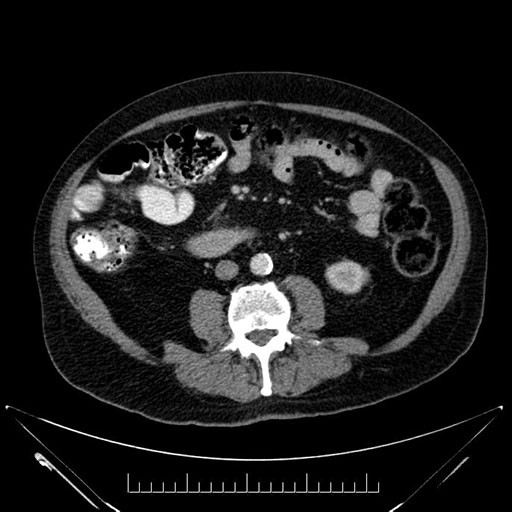

Imaging Analysis

Look through the patient's CT scan to identify any areas of concern for the necessary procedure.

Based on your CT findings, which issue(s) would give reason for "planned slowing down moment(s)" in this case?